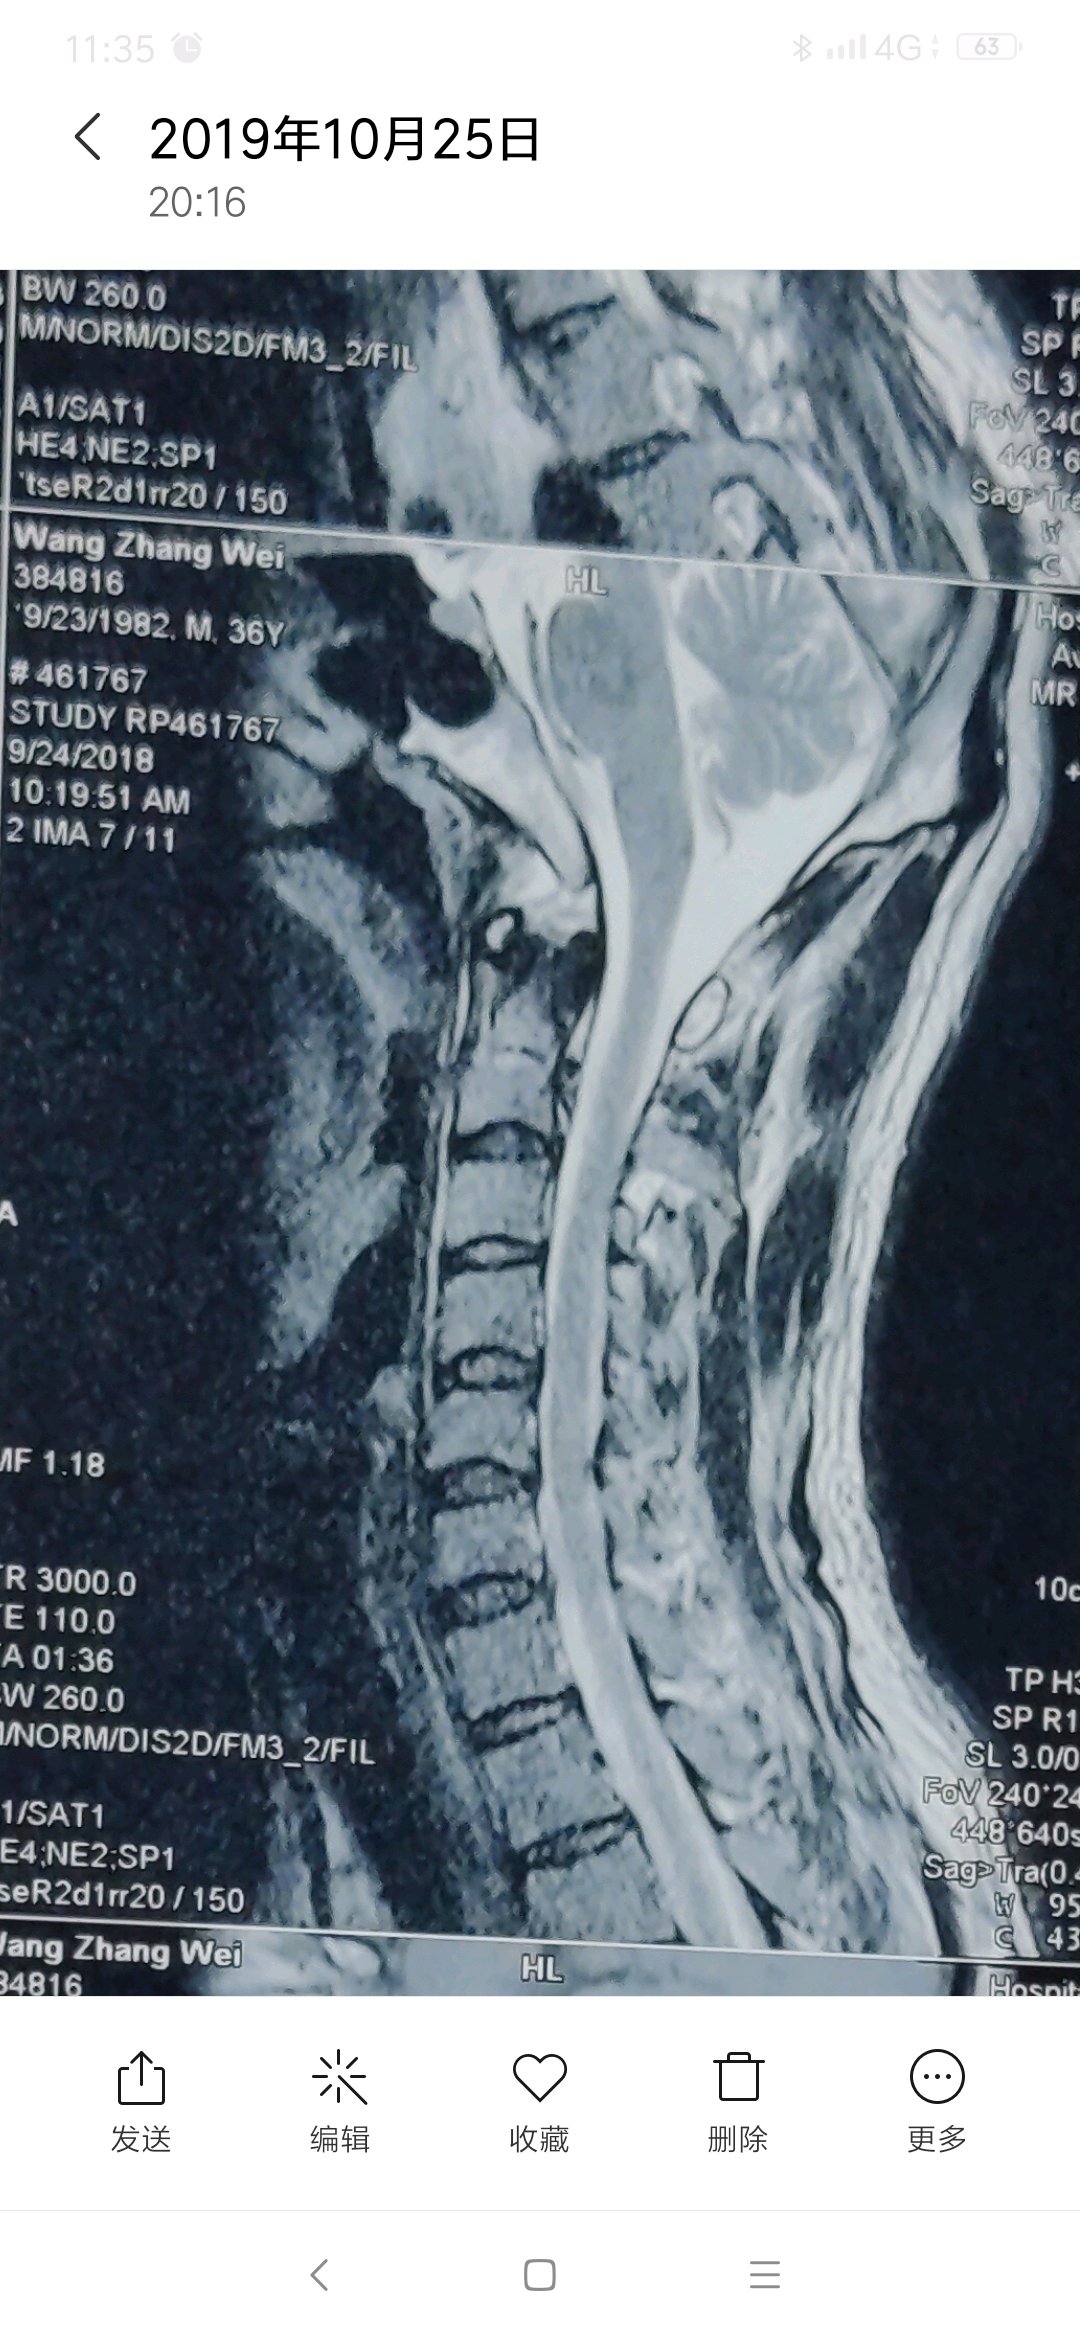

有专家吗,这个层度严重吗,怎么能治好,主要表现脖子疼痛,活动受限。

首先活动受限是扭头,低头仰头都受限?还是某个方向?

转头,抬头,低头,都会痛,疼痛主要在右侧

片子不严重,多锻炼就好了

每次去医院看病,医院都说不严重,可是痛起来真的太痛苦了。